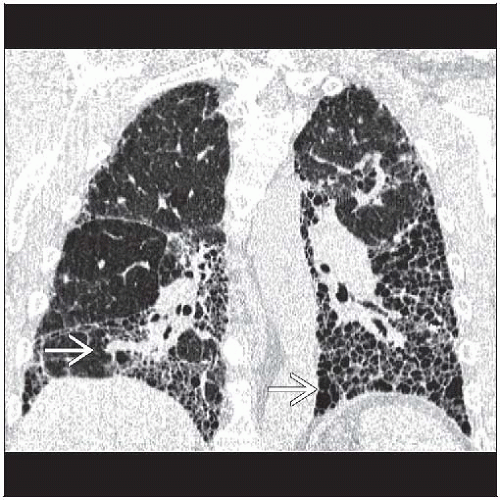

Living with Pulmonary Fibrosis Source: dresterle.com